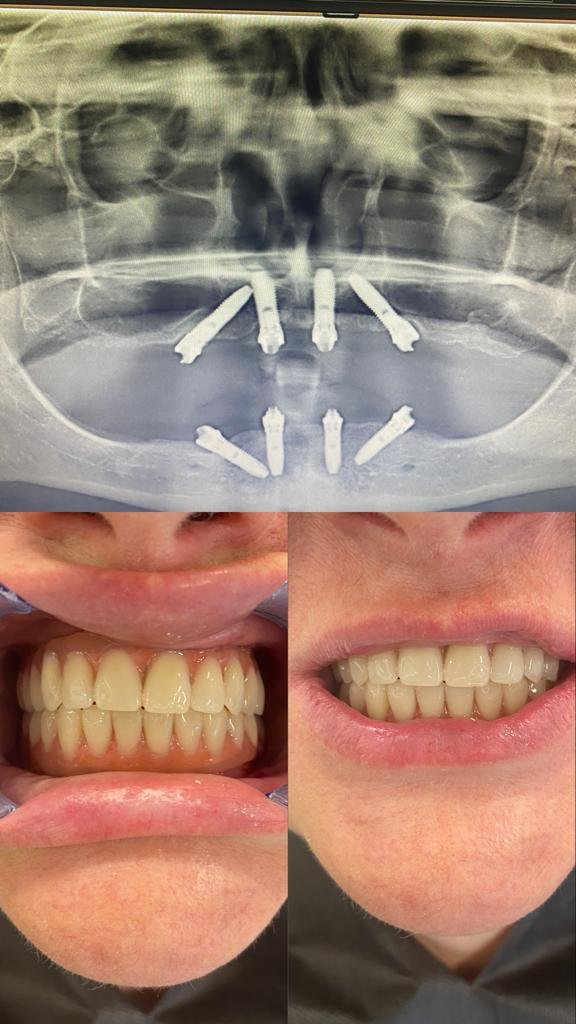

all on 4

All On Four prosedürü, cerrahi ve protez işlemleri olarak iki aşamadan oluşmaktadır. Tedavi günü hastaya planlamaya uygun şekilde 4 adet dental implant yerleştirildikten sonra aynı gün geçici diş protezi, dental implantların üstüne sabitlenir. 3 ay sonra ise hastaya daimi diş protezleri yapılır.